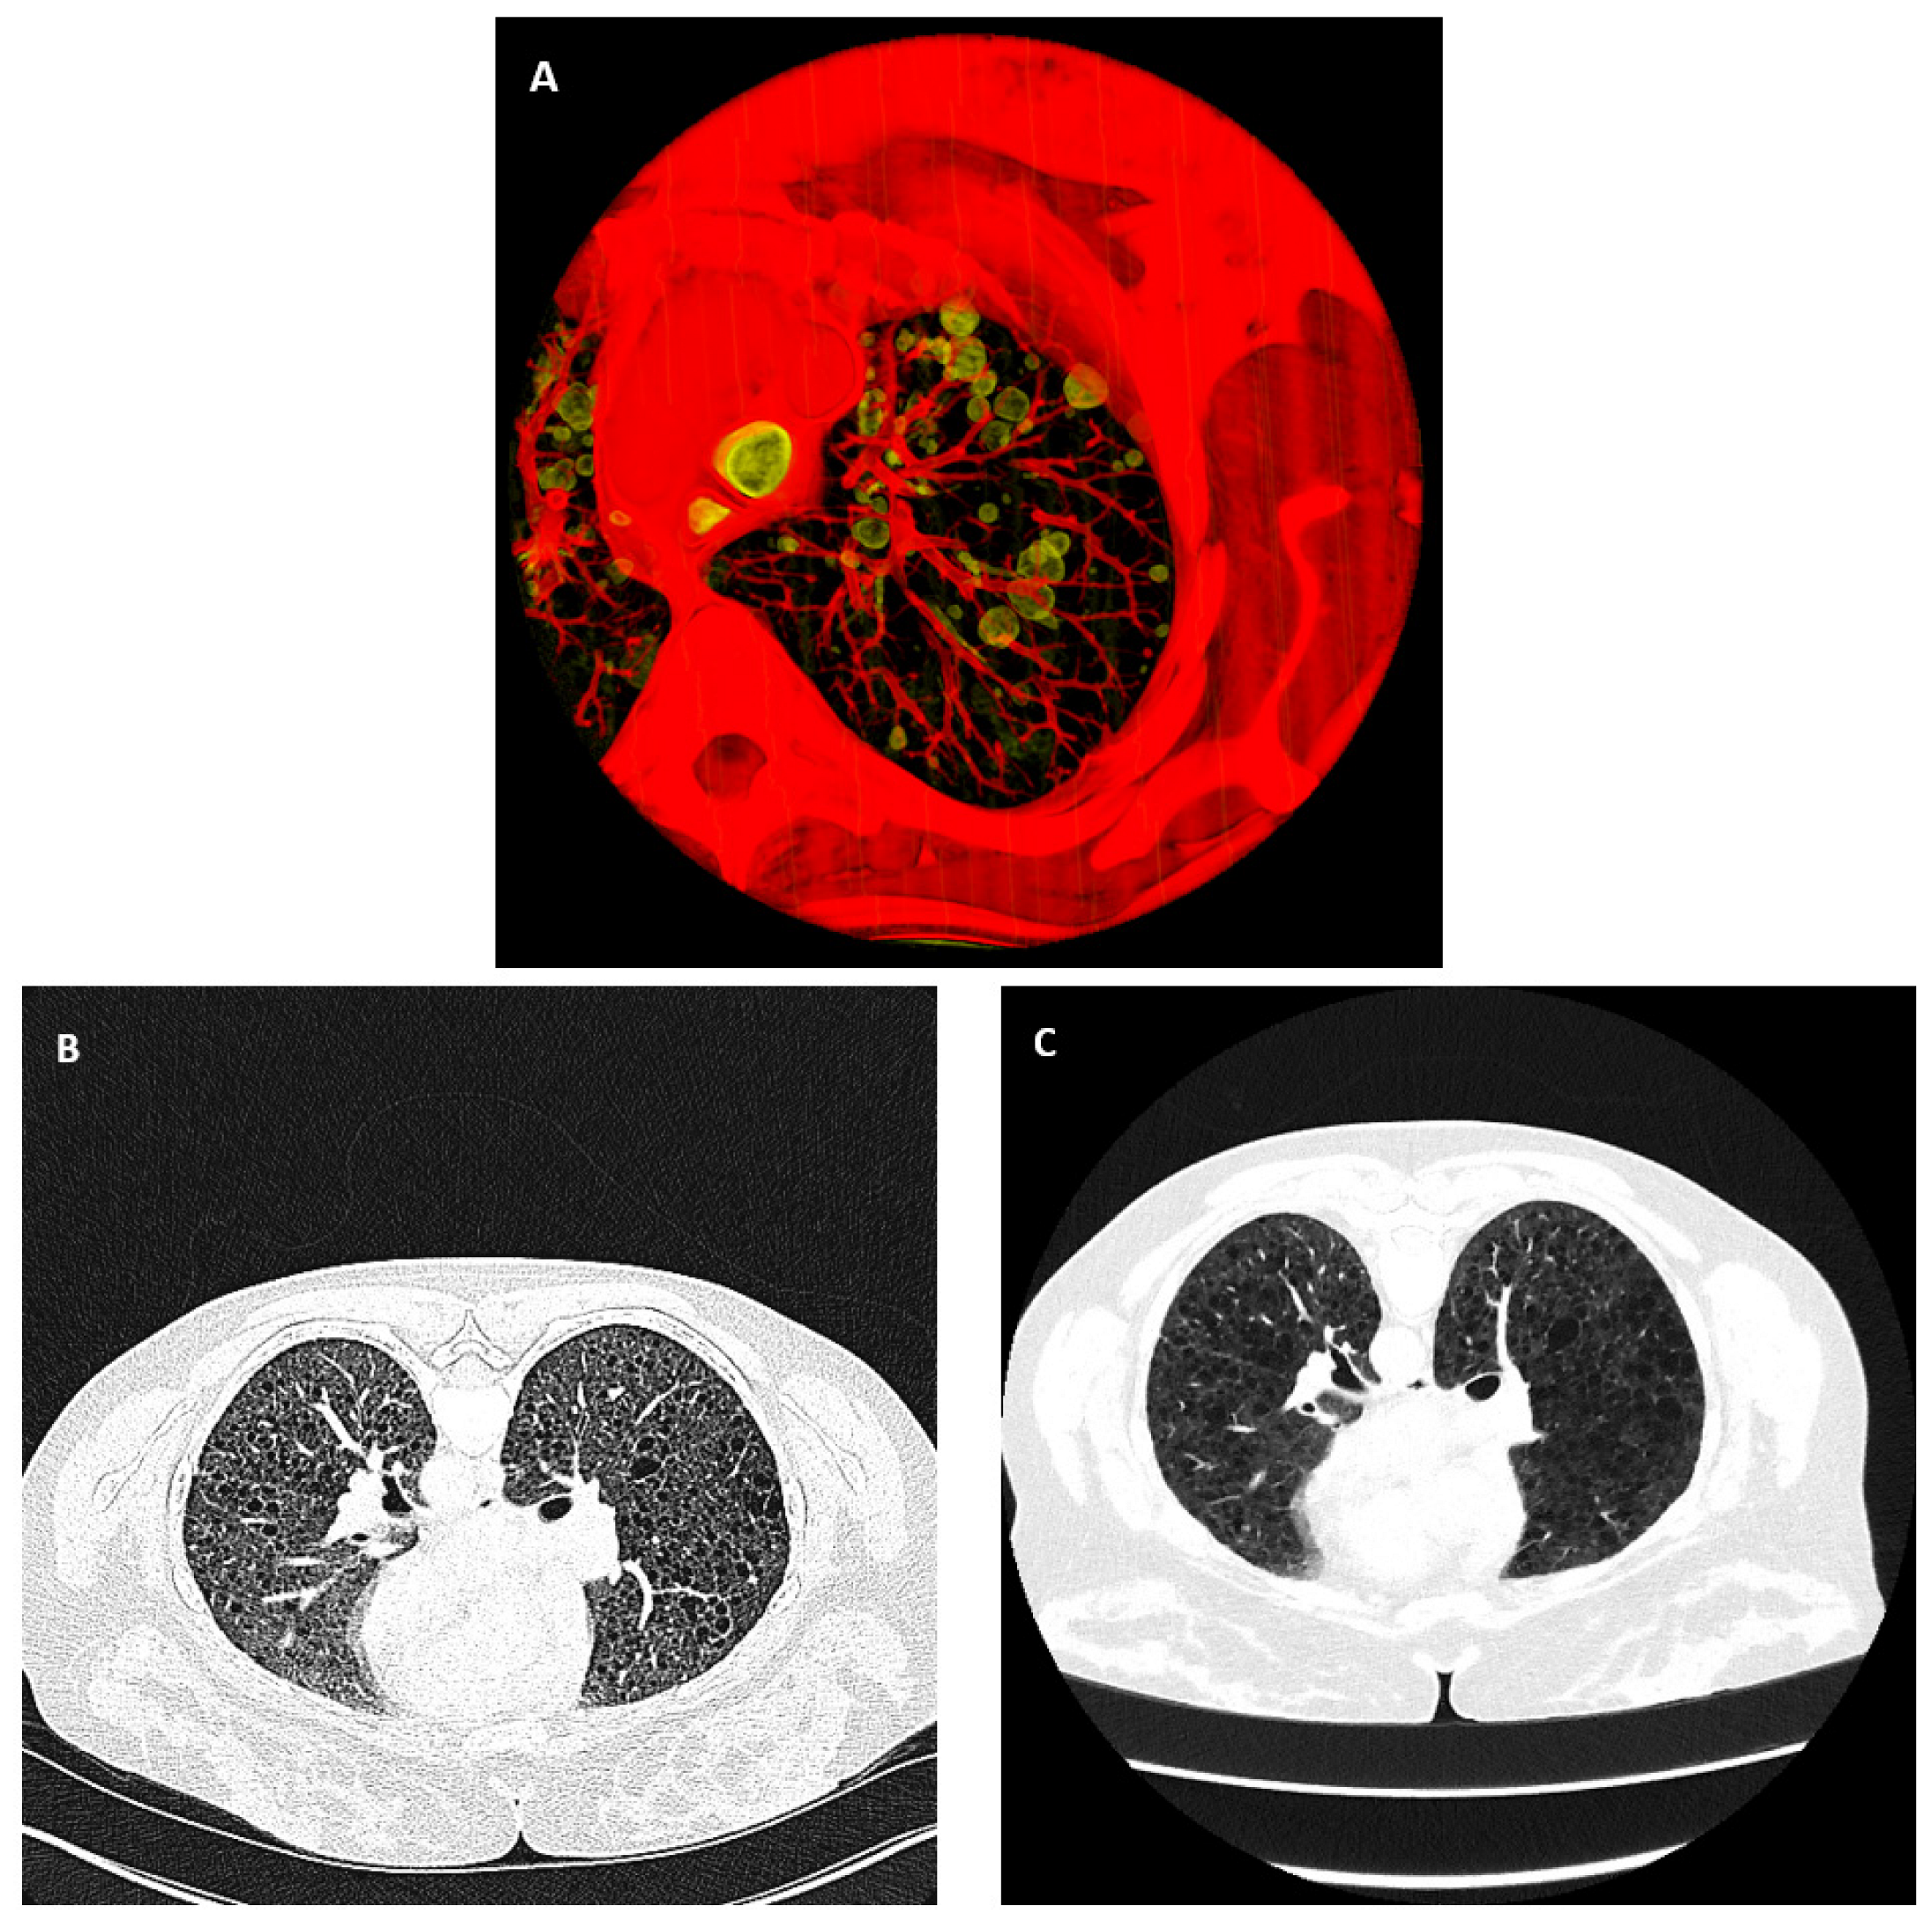

Figure 1.

Air-filled pulmonary cysts from the disease lymphangioleiomyomatosis and the variability of chest CT images over time and across different scanner platforms. (A) A three-dimensional rendered view of a portion of the lung from the chest CT scan of a patient. The bubble-like structures in the lung highlighted in yellow are air-filled cysts, a hallmark of the disease. (B,C) High-resolution CT images of the same location in the chest of the same patient were acquired 12 years apart from two different scanner platforms. Both are displayed in the grayscale range of −1100 HU to 0 HU. This is an example of the variability of image quality and characteristics.

To describe the level of variability in HRCT scans that we encountered in longitudinal studies, in a survey of 268 high-resolution chest CT (HRCT) image series from 24 LAM patients over a period of 23 years, we found them to be from 12 different scanner models from four different manufacturers (Ge Medical Systems LightSpeed Ultra, Ge Medical Systems LightSpeed QX/i, Ge Medical Systems HiSpeed CT/I, Ge Medical Systems Genesis_Hispeed_RP, Siemens Definition, Siemens Biograph128, Siemens Somatom Force, Siemens Somatom Definition Flash, Philips Brilliance 64, Philips Mx8000 IDT 16, Toshiba Aquilion One, and Canon Aquilion One/Prism). Eighteen different image reconstruction kernels were used at various times over the two decades. Of these image series, 39% were performed with contrast agents, with varying delays after contrast injection and levels of contrast enhancement of the lung tissue. An example of the diverse image quality and appearance is illustrated in Figure 1B,C. The two images were from the same patient. They were acquired on two different scanner models, 12 years apart.